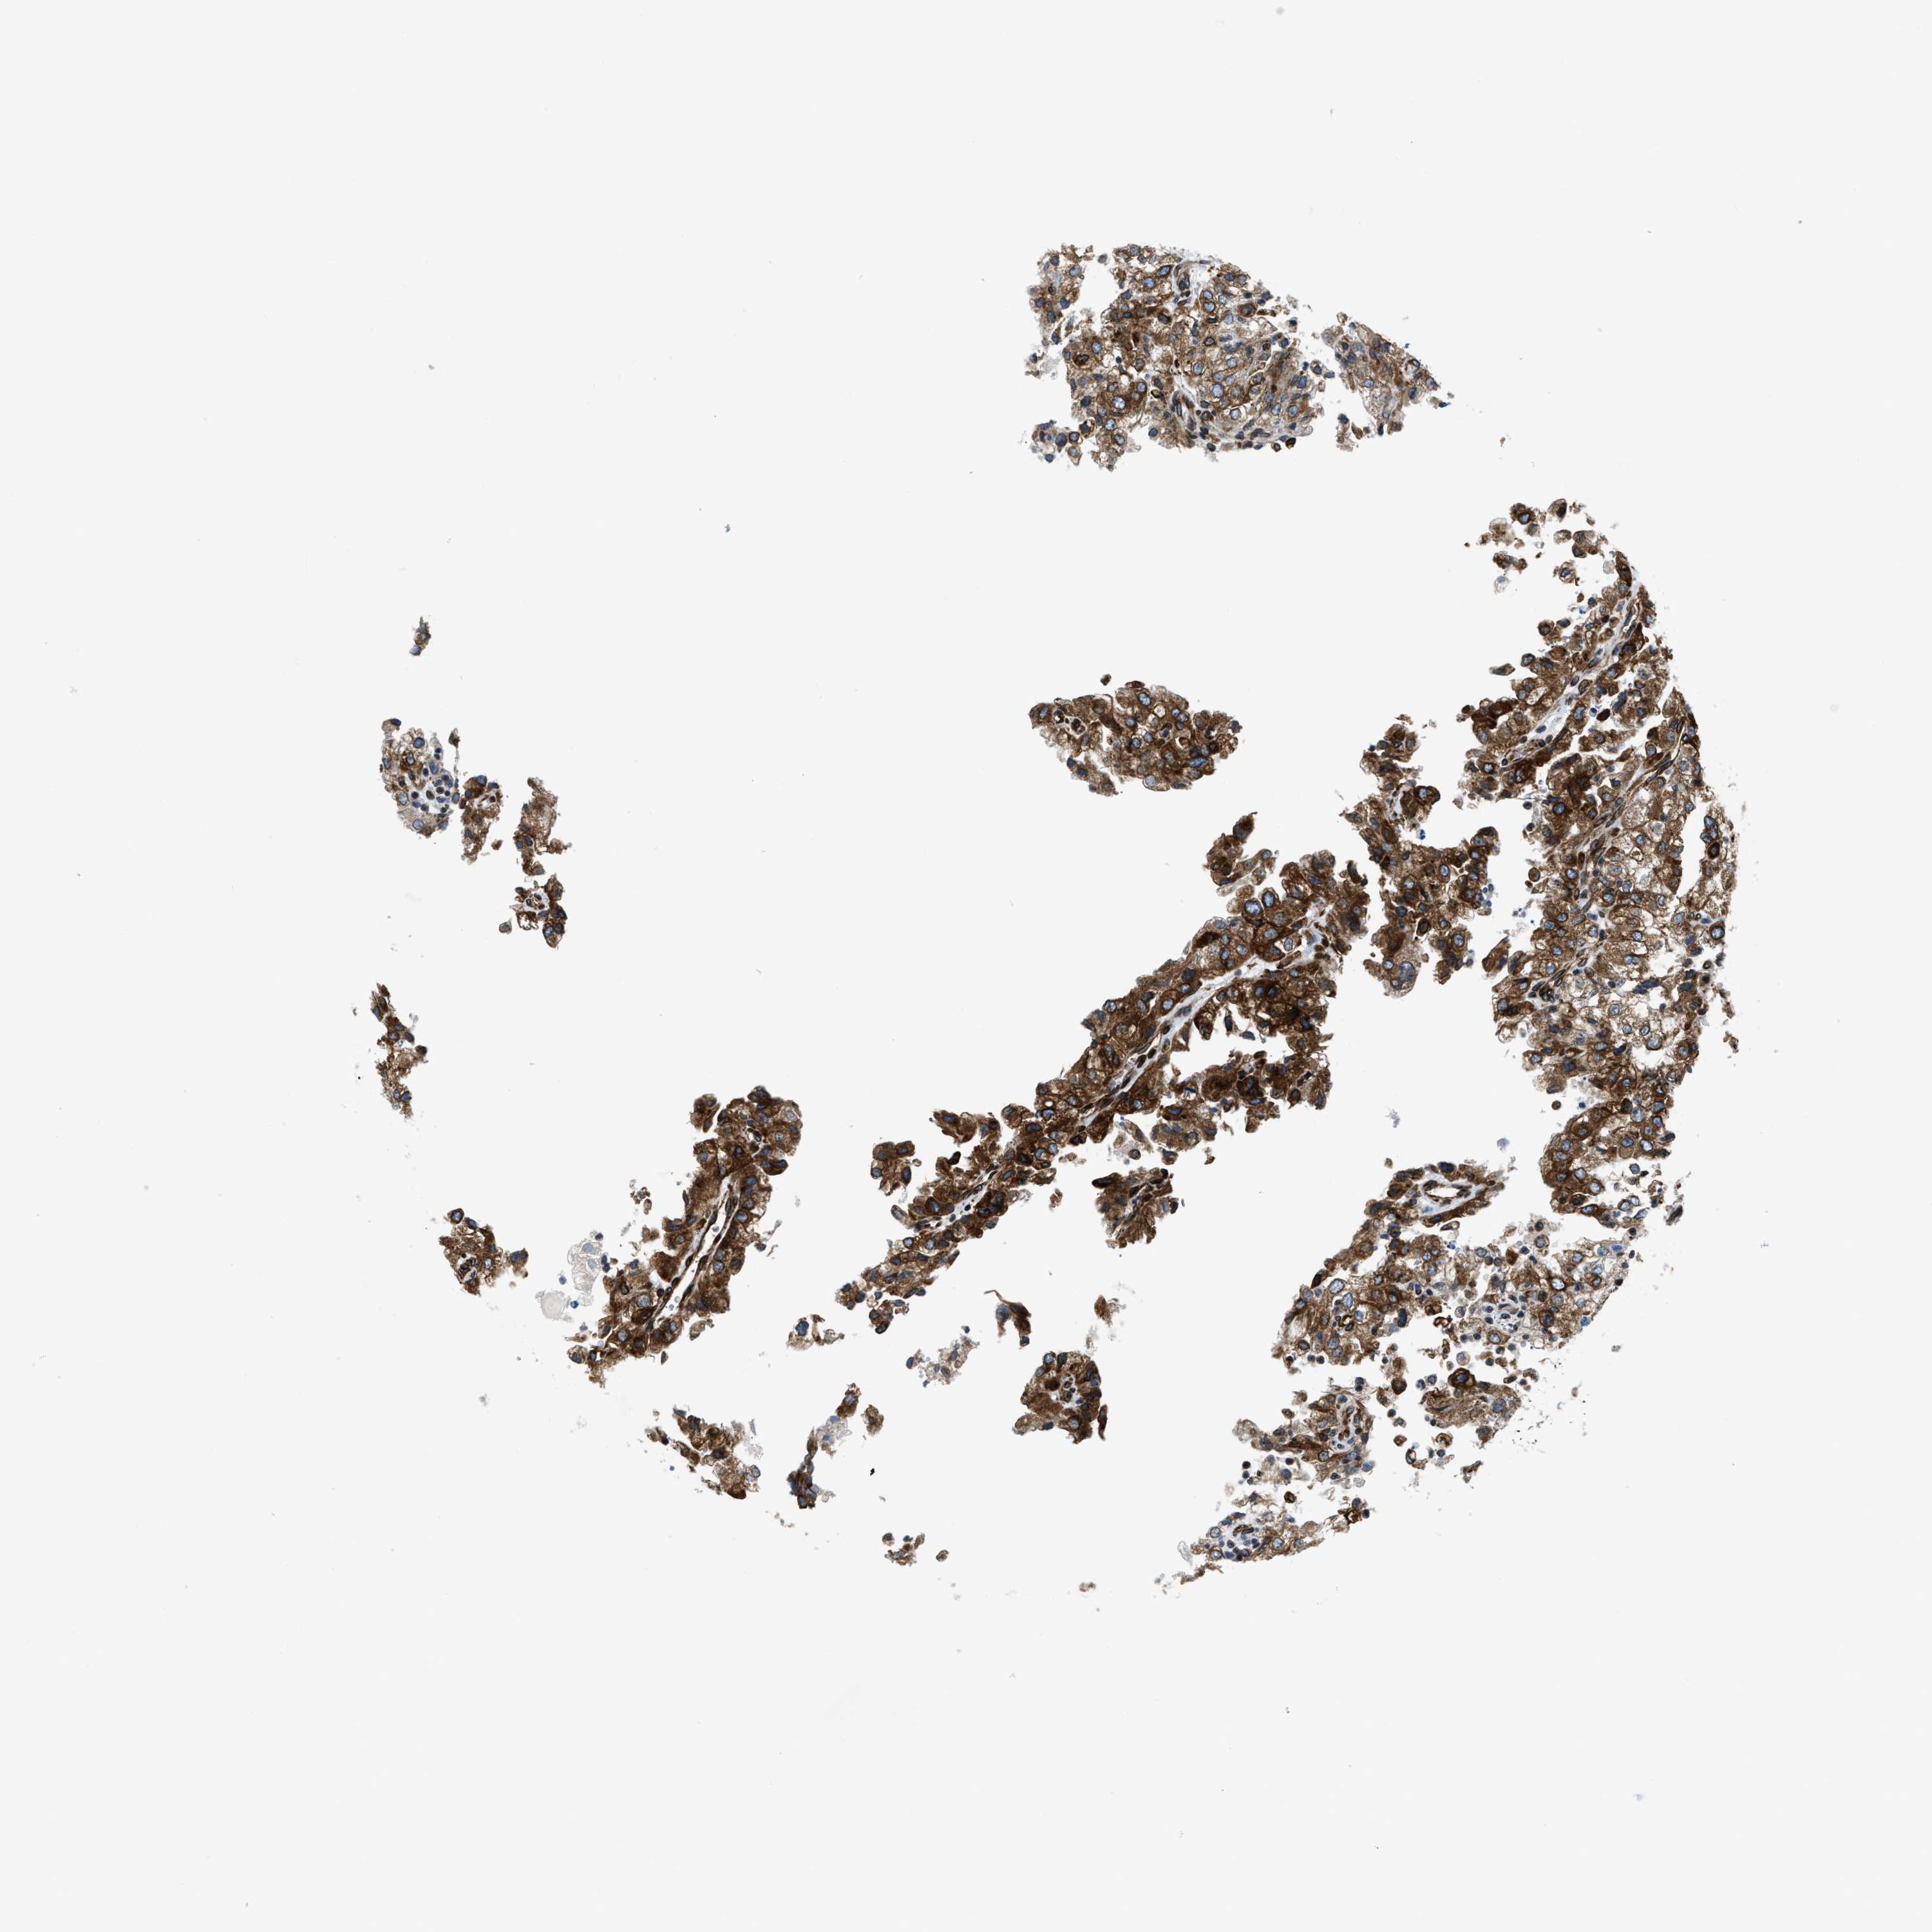

KIDNEY RENAL CLEAR CELL CARCINOMA (TCGA) - Interactive survival scatter ploti

The Survival Scatter plot shows the clinical status (i.e. dead or alive) for all individuals in the patient cohort, based on the same data that underlies the corresponding Kaplan-Meier plots. Patients that are alive at last time for follow-up are shown in blue and patients who have died during the study are shown in red.

The x-axis shows the expression levels (FPKM) of the investigated gene in the tumor tissue at the time of diagnosis. The y-axis shows the follow-up time after diagnosis (years). Both axes are complimented with kernel density curves demonstrating the data density over the axes. The top density plot shows the expression levels (FPKM) distribution among dead (red) and alive patients (blue). The right density plot shows the data density of the survived years of dead patients with high and low expression levels respectively, stratified using the cutoff indicated by the vertical dashed line through the Survival Scatter plot. This cutoff is automatically defined based on the FPKM cutoff that minimizes the p-score. The cutoff can be changed by dragging the vertical line or by entering a cutoff value in the square labeled "Current cut-off".

Under the Survival Scatter plot the p-score landscape (black curve; left axis) is shown together with dead median separation (red curve; right axis). Dead median separation is the difference in median mRNA expression between patients who have died with high and low expression, respectively. It is calculated as follows: median FPKM expression of dead patients with high expression - median FPKM expression of dead patients with low expression. This is intended to aid the user in visually exploring custom cutoffs and the associated p-scores and dead median separation.

Individual patient data is displayed and can be filtered by clicking on one or more of the category buttons on the top of the page. Categories describing expression level and patient information include: high, low, alive, dead, female, male and tumor stages. The scale of the x-axis can be toggled between linear and log-scale by clicking on the "x log" button. Mouse-over function shows TCGA ID, patient information and mRNA expression (FPKM) for each patient.

& Survival analysisi

Kaplan-Meier plots summarize results from analysis of correlation between mRNA expression level and patient survival. Patients were divided based on level of expression into one of the two groups "low" (under cut off) or "high" (over cut off). X-axis shows time for survival (years) and y-axis shows the probability of survival, where 1.0 corresponds to 100 percent.

CDS2 is validated prognostic, high expression is favorable in Kidney Renal Clear Cell Carcinoma (TCGA)

Best expression cut offi

Based on the FPKM value of each gene, patients were classified into two groups and association between prognosis (survival) and gene expression (FPKM) was examined. The best expression cut-off refers the FPKM value that yields maximal difference with regard to survival between the two groups at the lowest log-rank P-value. Best expression cut-off was selected based on survival analysis .

When clicking on this number, the vertical dashed line indicating cut-off, the interactive survival plot, and the Kaplan-Meier curve will be adjusted to show results based on the best expression cut-off.

: 19.31

TCGA RNA samplesi

RNA-seq data is reported as average FPKM (number Fragments Per Kilobase of exon per Million reads), generated by the The Cancer Genome Atlas (TCGA) .

Normal distribution across the dataset is visualized with box plots, shown as median and 25th and 75th percentiles. Points are displayed as outliers if they are above or below 1.5 times the interquartile range. FPKM values of the individual samples are presented next to the box plot.

Average pTPM 15.8

Number of samples 521